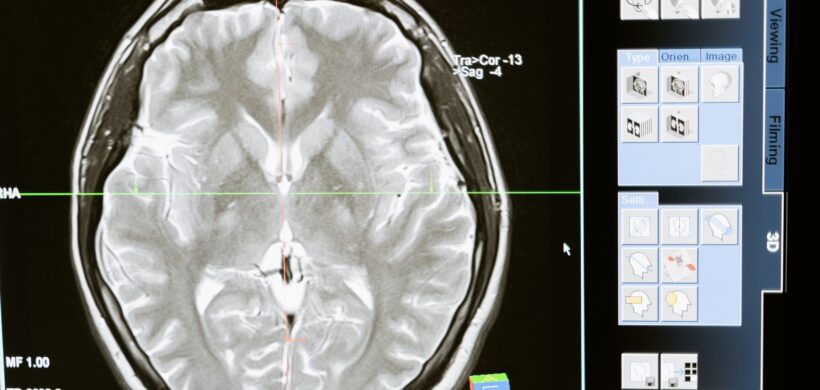

Alteraciones en la materia blanca y materia gris del cerebro y su impacto en la cognición

Lizbeth De la Torre López | Neuropsicóloga Las diferentes áreas del cerebro son responsables de diversas funciones, la materia gris (MG) y la materia blanca (MB) desempeñan un papel importante en todos los aspectos de la vida humana [1]. La MB constituye una red de fibras nerviosas que permite el intercambio de información y la comunicación entre diferentes áreas de la MG [2] responsable del procesamiento de la información, la función cognitiva y la función motora. Mientras que los neurocientíficos han considerado durante mucho tiempo que la corteza cerebral es el principal centro de la función cognitiva, cada vez se reconoce más que la MB y MG del cerebro son igualmente importantes para la cognición [3]. Las vías de la MG median la conectividad esencial que organiza el comportamiento humano, trabajando en conjunto con la MG para permitir el extraordinario repertorio de capacidades cognitivas humanas. Existen numerosas pruebas, revisadas desde la neurología conductual, de que las lesiones y disfunciones de la MB y MG están relacionadas con trastornos neurodegenerativos, incluida la enfermedad de Alzheimer [4]. En el mismo sentido, las lesiones graves de la MB se asocian con deterioro cognitivo, deterioro funcional global, accidentes cerebrovasculares, trastornos del estado de ánimo y disfunciones de la marcha y el equilibrio. Las lesiones de la MB también se asocian con atrofia de la MG y neurodegeneración acelerada. Investigaciones recientes indican que las lesiones de la MB y la MG relacionadas con la edad son irreversibles y progresivas. Por lo tanto, es importante debatir los conceptos emergentes sobre la prevención y el tratamiento de la disfunción cognitiva asociada a los trastornos de la MB y MG [5]. Los estudios coinciden, entre otras cosas, en las siguientes sugerencias para prevenir las alteraciones cognitivas relacionadas con la MB y la MG: Las actividades físicas aeróbicas que mejoran la capacidad cardiorrespiratoria son beneficiosas para la función cognitiva en adultos mayores sanos, con efectos observados en la función motora, la velocidad cognitiva, las funciones de memoria diferida y la atención auditiva y visual [6]. Evitar el endurecimiento arterial central, que está asociado con el daño de la MB y la pérdida de volumen de la MG en las personas mayores, además de estar relacionado con las enfermedades cerebrovasculares. Esto puede lograrse mediante un enfoque holístico del estilo de vida centrado en el ejercicio aeróbico regular, una dieta mediterránea rica en vegetales, dejar de fumar, controlar el peso, controlar la presión arterial y limitar el consumo de sal, además de considerar suplementos como las vitaminas D y K para ayudar a controlar el calcio y reducir la calcificación, todos ellos cruciales para mantener la flexibilidad de las arterias [7]. Por último, pero no menos importante, se recomienda adoptar una postura vigilante ante los cambios relacionados con el estado emocional como parte de un estilo de vida con salud integral, ya que la depresión y la fatiga se asociaron con diversos cambios en la integridad de la sustancia blanca, que se correlacionaron con biomarcadores bioquímicos relacionados con la inflamación [8]. Una vez que se producen lesiones en la MB/MG, estas son irreversibles [9], de ahí la importancia de tener en cuenta todos los hábitos de vida relacionados con la prevención de su deterioro. Los estudios indican que el control de los factores de riesgo modificables, por ejemplo, mediante una dieta saludable o la práctica de ejercicio físico, representa una valiosa estrategia de prevención para cuidar la cognición desde lo más profundo. Referencias Mercadante AA, Tadi P. Neuroanatomy, Gray Matter. [Updated 2023 Jul 24]. In: StatPearls [Internet]. Treasure Island (FL): StatPearls Publishing; 2025 Jan-. Available from: https://www.ncbi.nlm.nih.gov/books/NBK553239/ Chiao CC, Lin CI, Lee MJ. Multiple Approaches for Enhancing Neural Activity to Promote Neurite Outgrowth of Retinal Explants. Methods Mol Biol. 2020;2092:65-75. [PubMed] Filley CM, Fields RD. White matter and cognition: making the connection. J Neurophysiol. 2016 Nov 01;116(5):2093-2104. [PMC free article] [PubMed] Wang Y, Metoki A, Alm KH, Olson IR. White matter pathways and social cognition. Neurosci Biobehav Rev. 2018 Jul;90:350-370. doi: 10.1016/j.neubiorev.2018.04.015. Epub 2018 Apr 20. PMID: 29684403; PMCID: PMC5993647. Habes M, Erus G, Toledo JB, Zhang T, Bryan N, Launer LJ, Rosseel Y, Janowitz D, Doshi J, Van der Auwera S, von Sarnowski B, Hegenscheid K, Hosten N, Homuth G, Völzke H, Schminke U, Hoffmann W, Grabe HJ, Davatzikos C. White matter hyperintensities and imaging patterns of brain ageing in the general population. Brain. 2016 Apr;139(Pt 4):1164-79. doi: 10.1093/brain/aww008. Epub 2016 Feb 24. PMID: 26912649; PMCID: PMC5006227. Angevaren M, Aufdemkampe G, Verhaar HJ, Aleman A, Vanhees L. Physical activity and enhanced fitness to improve cognitive function in older people without known cognitive impairment. Cochrane Database Syst Rev. 2008 Apr 16;(2):CD005381. doi: 10.1002/14651858.CD005381.pub2. Update in: Cochrane Database Syst Rev. 2008 Jul 16;(3):CD005381. doi: 10.1002/14651858.CD005381.pub3. PMID: 18425918. Won J, Tomoto T, Shan K, Tarumi T, Zhang R. Associations of Central Arterial Stiffness With Brain White Matter Integrity and Gray Matter Volume in MRI Across the Adult Lifespan. J Magn Reson Imaging. 2025 Jul;62(1):215-229. doi: 10.1002/jmri.29713. Epub 2025 Jan 10. PMID: 39792583; PMCID: PMC12178825. Lin C, Yeh FC, Glynn NW, Gmelin T, Wei YC, Chen YL, Huang CM, Shyu YC, Chen CK. Associations of depression and perceived physical fatigability with white matter integrity in older adults. Psychiatry Res Neuroimaging. 2024 Jun;340:111793. doi: 10.1016/j.pscychresns.2024.111793. Epub 2024 Feb 10. PMID: 38373367; PMCID: PMC11842153. Hasan TF, Barrett KM, Brott TG, Badi MK, Lesser ER, Hodge DO, Meschia JF. Severity of White Matter Hyperintensities and Effects on All-Cause Mortality in the Mayo Clinic Florida Familial Cerebrovascular Diseases Registry. Mayo Clin Proc. 2019 Mar;94(3):408-416. doi: 10.1016/j.mayocp.2018.10.024. PMID: 30832790. Pulsa para leer el artículo en inglés